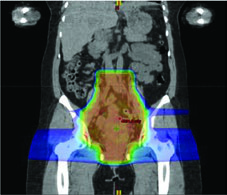

A terapia com prótons aproveita um build-up de dose relativamente gradual e uma queda de dose abrupta distal ao alvo em comparação com fótons. Essa propriedade física fundamental permite reduzir a dose nos OARs — especialmente distais aos campos de tratamento — e diminuir a dose integral, preservando cobertura adequada dos alvos.

Cenários em que prótons podem oferecer vantagem sobre IMRT incluem tratamento de linfonodos para-aórticos e reirradiação. Estudos dosimétricos e clínicos iniciais mostram melhora na dose em estruturas normais adjacentes, incluindo intestino, bexiga e medula óssea. Prótons também permitem melhor preservação ovariana em mulheres pré-menopáusicas — por exemplo, poupando um ovário com dose média inferior a 15 Gy.

Para o tratamento definitivo, a dosimetria-alvo deve ser idêntica à utilizada com fótons, corrigida pela efetividade biológica relativa (RBE) assumida de 1,1 para prótons. O delineamento de GTV e CTV segue os mesmos princípios do capítulo de EBRT definitiva. Os PTVs são específicos por feixe, baseados na incerteza de alcance. Um cuidado fundamental: evitar arranjos de feixe que coloquem estruturas críticas no campo distal ao alvo.

A terapia com prótons pode ser considerada como alternativa de boost para pacientes que não podem receber braquiterapia. Prótons apresentam vantagens dosimétricas em bexiga, intestino, cabeças femorais e reto em comparação ao VMAT. O CTV de boost pode ser determinado por RM obtida após 3 semanas de quimiorradiação, administrando-se então 30 Gy/Gy equivalente em 5 frações em substituição à braquiterapia. Entretanto, evidência prospectiva de alta qualidade ainda é insuficiente, e a relação entre dosimetria melhorada e redução clinicamente significativa de toxicidade permanece sem comprovação definitiva.